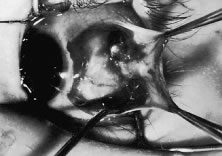

RESECTION PROCEDURE: LIMBAL APPROACH

Incision is made into the conjunctiva at the limbus (Fig. 64).

|

The assistant elevates the conjunctiva while the surgeon uses a Stevens' hook to elevate the rectus muscle (Fig. 65). A Jameson muscle hook is passed under the muscle tendon in a plane that is tangential to the scleral surface, about 3 mm behind the tented rectus muscle insertion. Figure 66 shows the rectus muscle on the Jameson hook.

|

The surgeon cuts the intermuscular septa free from the muscle capsule (Fig. 67). A Castroviejo caliper is used to measure the amount of tendon that will be resected (Fig. 68). A Jameson resection clamp is placed on the muscle at the point of anticipated resection. Measurement is made from the portion of tendon that is on the posterior edge of the Jameson hook to the resection clamp. Exposure is facilitated with a Desmarres retractor.

|

|

The muscle is cut free from its insertion (Fig. 69). The surgeon holds the Jameson clamp to elevate the muscle from the globe, and, using the other hand, the surgeon cuts the muscle free from the globe. The muscle stump is cut so that it is flush with the globe.

|

The globe is stabilized with a 0.5-mm-toothed Castroviejo forceps (Figs. 70 and 71). A mattress stitch with a double-armed 6-0 synthetic absorbable suture is placed through the most inferior portion of the insertion. The second needle is passed 1 mm below the central portion of the insertion. The initial penetration of the needle is just anterior to the insertion, and a secure bite is taken of the former insertion so that the needle exits just posterior to the old insertion. The needle is then passed underneath the Jameson resection clamp through muscle tendon, and the two sutures are held with a bulldog clamp to keep them separate from the sutures that are later passed through the upper pole of the insertion. Figure 71 shows the sutures being tied. This maneuver will effectively bring the resected muscle tendon up so that it can be reinserted at the insertion. Once the muscle is tied securely, the Jameson resection clamp is released and then advanced to the cut end of the insertion (Fig. 72). Under direct visualization, a Westcott scissors is used to trim the excess muscle stump. Care is taken to leave at least 1 mm of muscle tendon in front of the two sutures that secure the muscle to the insertion. After the muscle stump has been inspected, the conjunctiva is advanced back to the limbus (Fig. 73). Two 8-0 collagen sutures are used to secure the conjunctiva at the limbus. The small open radial portion of the incision will heal without suture closure. If the surgeon “buries the knots” under the conjunctiva near the limbus, the patient will have less foreign body sensation. Figure 74 shows the eye immediately after a recess-resect procedure. The conjunctiva should be smooth at the limbus to prevent disruption of the tear layer and formation of dellen. The eye is not patched. Antibiotic drops or antibiotic-steroid drops may be used at the discretion of the surgeon.